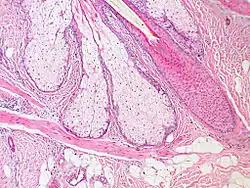

| Arrector pili muscle | |

|---|---|

Base of pilosebaceous unit: An arrector pili muscle can be seen as the pink-staining band of tissue at the bottom center and bottom left of image | |